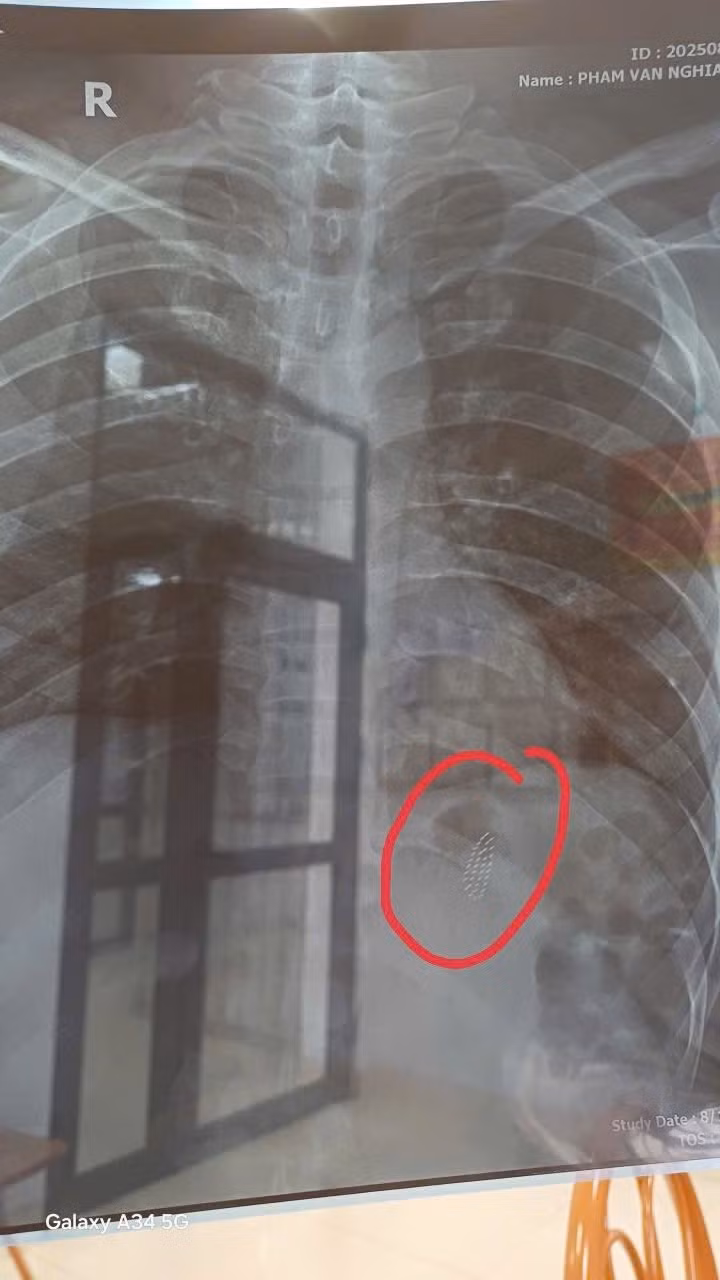

Bàn chải đánh răng trên phim chụp - Ảnh BVCC

Trực tiếp thực hiện thủ thuật là BS Trần Mạnh Hùng, Phó Trưởng khoa Chẩn đoán hình ảnh cho biết, quá trình can thiệp gặp nhiều khó khăn do bàn chải có kích thước 15 x 2 cm, nằm ngang ở thân vị dạ dày;

Dị vật dài, trơn trượt, gây khó cho việc đưa dụng cụ tiếp cận và gắp đúng đầu bàn chải; Nguy cơ dị vật cọ xát, làm tổn thương tâm vị và thực quản khi kéo ra ngoài.